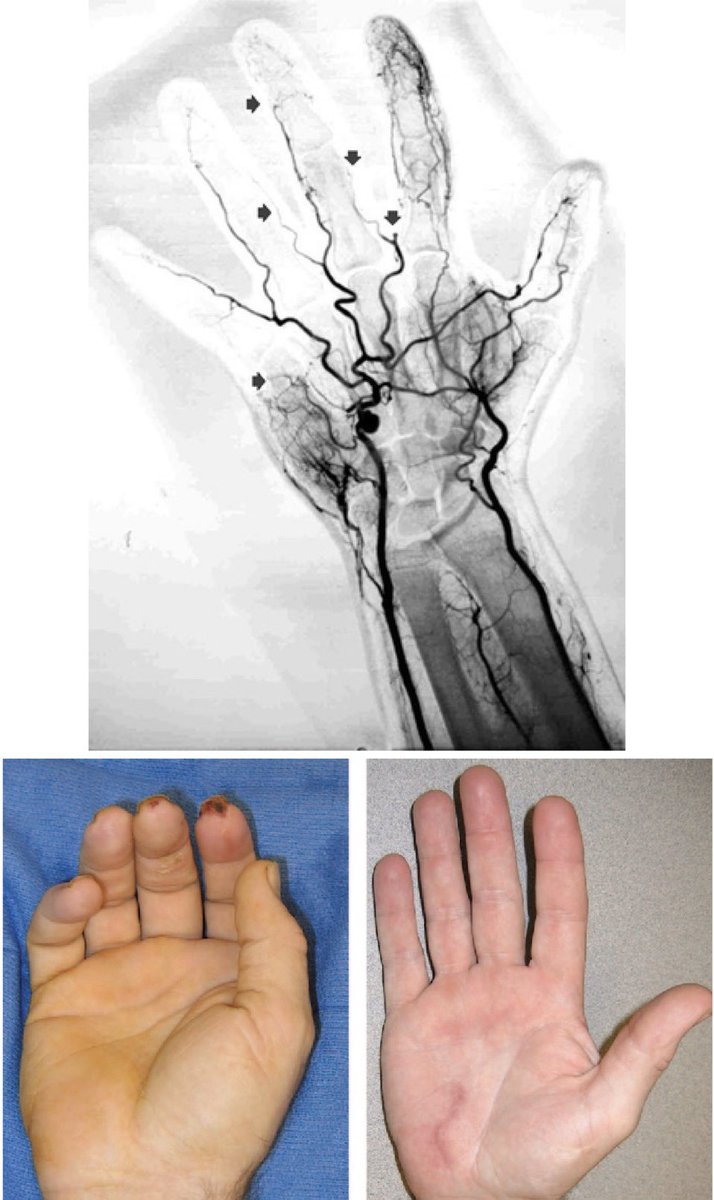

Dr.OMID BANDARCHI ,M.D. on Twitter "🛑Hypothenar hammer syndrome(HHS

Dr.OMID BANDARCHI ,M.D. on Twitter "🛑Hypothenar hammer syndrome(HHS Jack Hammer Syndrome Nutcracker or jackhammer esophagus targets the smooth muscles that usually move food seamlessly from your throat down to your stomach. Hypercontractile esophagus (nicknamed jackhammer esophagus) is a recently defined disease within the esophageal motility. Jackhammer esophagus is one of several dysmotility disorders of the esophagus that are specifically recognized and diagnosed with. Hypercontractile esophagus, also known as jackhammer esophagus, is. Jack Hammer Syndrome.